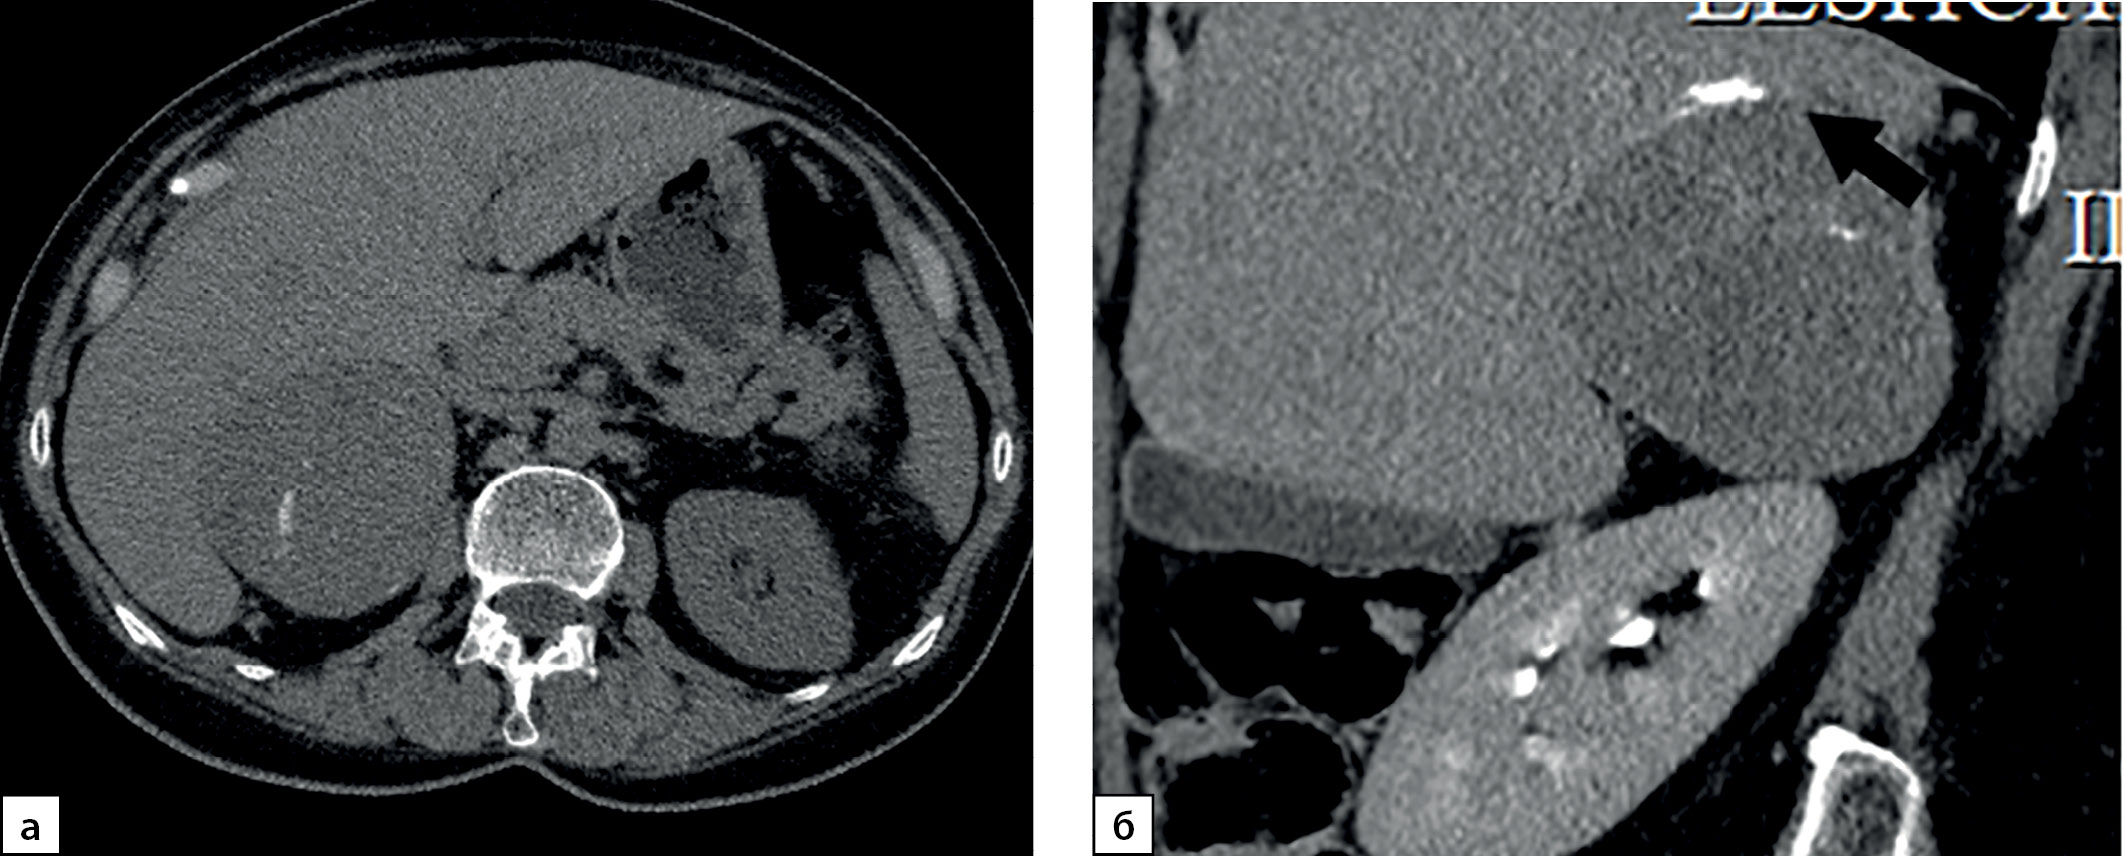

Рисунок 3. Компьютерные томограммы пациентки И., 67 лет с малыми размерами адренокортикальной карциномы (28х35 мм), распространяющейся из латеральной ножки левого надпочечника вдоль передней поверхности почки: а — изображение в аксиальной плоскости, нативная фаза сканирования — показатели плотности до 16 HU; б — артериальная фаза постконтрастного сканирования; в — венозная фаза; г — фаза отсроченного сканирования, коэффициент абсолютного вымывания контрастного препарата составил 42%, относительного — 31,8%.

Figure 3. Computed tomography of patient I., 67 years old, with small size adrenocortical carcinoma (28x35 mm), spreading from the lateral pedicle of the left adrenal gland along the anterior surface of the kidney: a — image in the axial plane, native scanning phase — density values up to 16 HU; b — arterial phase of post-contrast scanning; c — venous phase; d — phase of delayed scanning, the coefficient of absolute washout of the contrast agent was 42%, relative — 31.8%.

Рисунок 4. Компьютерные томограммы пациентки Ч., 42 лет с небольшой адренокортикальной карциномой (32х28 мм), с гетерогенной опухолевой тканью, распространяющейся до ворот почки: а — изображение в аксиальной плоскости, нативная фаза сканирования, плотность от +8,4 до +38HU; б — артериальная фаза постконтрастного сканирования; в — венозная фаза; г — фаза отсроченного сканирования, д — изображение реформатированное в косой сагиттальной плоскости, венозная фаза сканирования, образование локально деформирует почечную вену (стрелка). Коэффициент абсолютного вымывания контрастного препарата составил 56%, относительного — 36%.

Figure 4. Computed tomography of patient Ch., 42 years old, with a small adrenocortical carcinoma (32x28 mm), with heterogeneous tumor tissue extending to the hilum of the kidney: a — image in the axial plane, native scanning phase, density from +8.4 to +38HU ; b — arterial phase of post-contrast scanning; c — venous phase; d — phase of delayed scanning, e — image reformatted in the oblique sagittal plane, venous phase of scanning, the mass locally deforms the renal vein (arrow). The coefficient of absolute washout of the contrast agent was 56%, relative — 36%.